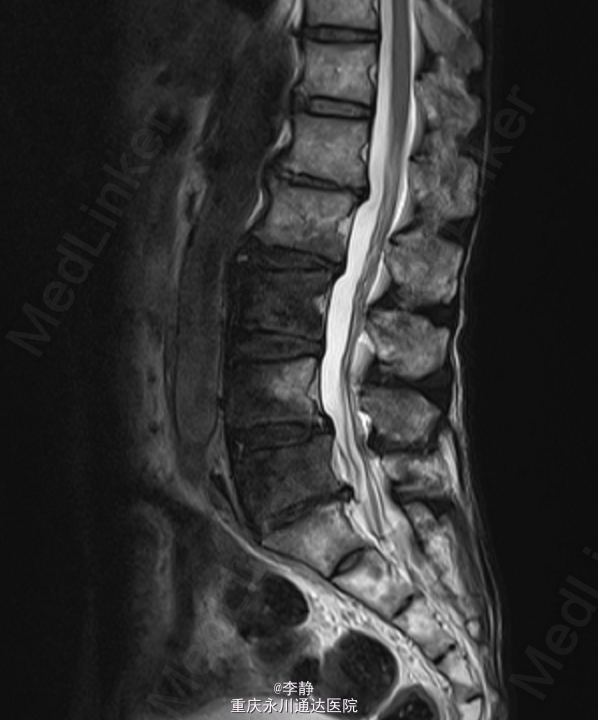

PET-CT:右肺肿块,考虑周围型肺癌,右肺门及纵膈多发淋巴结转移,T1及T2椎体及右侧附件骨转移;左颈部肿块针吸穿刺病理:转移性腺癌.

初步诊断:1.胸椎肿瘤:转移癌/肺恶性肿瘤。全身麻醉下行“胸椎恶性肿瘤后路肿瘤切除,椎管减压、内固定术”,术中予椎体内填充骨水泥,C5,C6,C7各打入一枚颈椎侧块螺钉,T3、T4两侧各打入一枚椎弓根螺钉,C臂机透视提示螺钉位置可。

术中冰冻:胸1,2椎肿瘤(2):显著增生的纤维结缔组织内有少量异型细胞,考虑转移性低分化腺癌。术后予锋替新2.0g ivgtt bid预防感染及镇痛,补液改善循环,促进愈合治疗等对症治疗。术后复查胸椎片:颈、胸椎后路术改变,术后内固定在位,胸1、2椎体内见高密度影。胸椎顺列。所见椎间隙无殊。